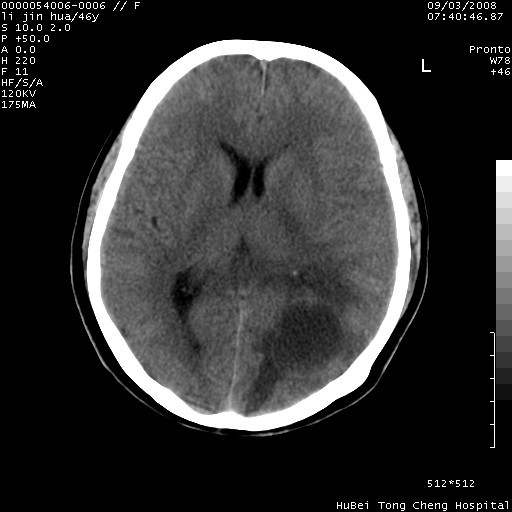

以下是引用panyishengct在2008-9-6 1:47:00的发言:[br]病史?[br]左侧枕/顶叶见一等/低混杂密度占位,壁完整,厚薄较均匀,其前方似有一类似小病灶,周围有水肿带,请结合病史考虑,脓肿可能,不排外转移瘤或胶质瘤,建议增强扫描。